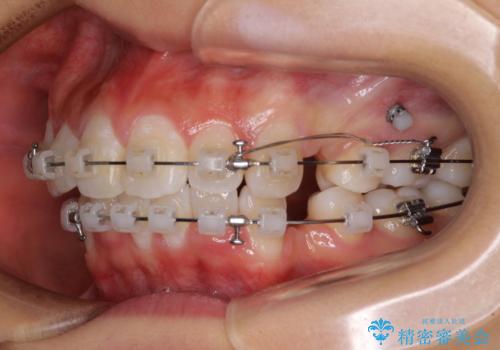

- クリアブラケット

- 1年7ヶ月

口元の突出感を改善するため、上下左右第一小臼歯4本の抜歯を行い、ワイヤー装置による矯正治療を行うこととしました。

治療前の上下正中はずれていましたが、骨格的な上下左右差はあまり認められなかったため、正中を揃えて治療を終えることができました。